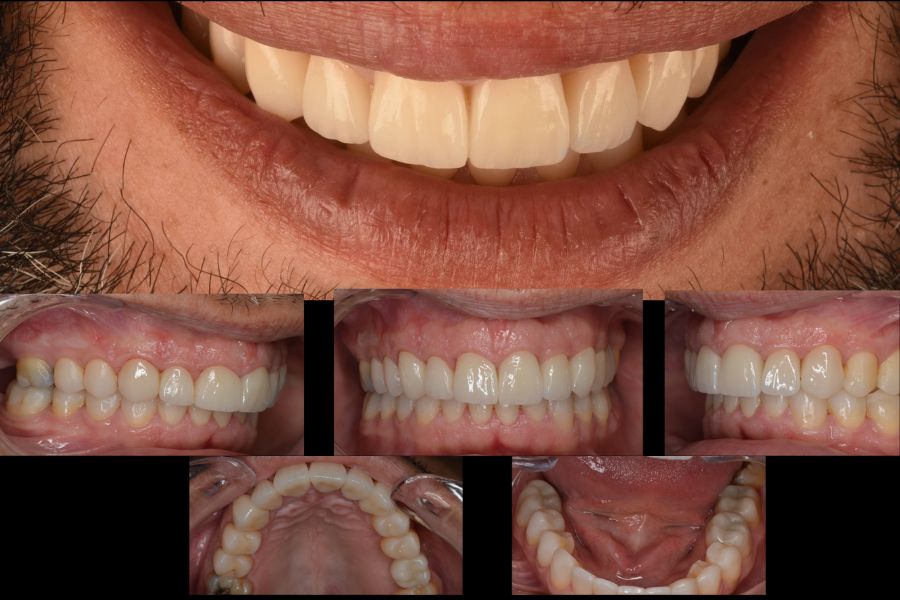

Resultado del tratamiento

Una vez finalizada la planificación, llevamos a cabo el tratamiento de forma secuencial y controlada:

- Ortodoncia para alinear y preparar la oclusión.

- Alargamiento coronario en todo el sector anterior.

- Férula para estabilizar la mandíbula y la mordida.

- Implante dental para reponer el molar superior ausente.

- Coronas dentales en la arcada superior.

- Carillas dentales en la arcada inferior.

Antes y después del tratamiento

Las últimas imágenes muestran el resultado final del tratamiento. El paciente logró una sonrisa equilibrada, con proporciones naturales y una mordida estable.

La mejora no fue solo estética, también recuperó la función masticatoria y una gran sensación de confort al cerrar y abrir la boca.

Este caso refleja cómo Smilecloud actúa como eje central del diagnóstico y la planificación, integrándose con otras tecnologías avanzadas para ofrecer tratamientos personalizados, precisos y previsibles.